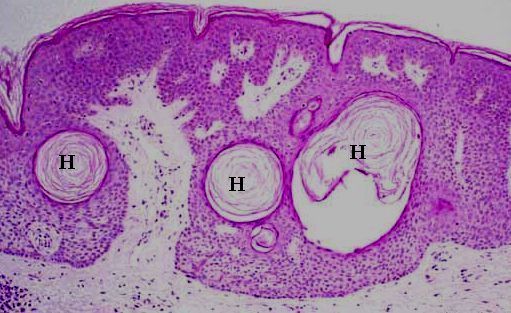

Histologically, seborrheic keratosis has the following features:

• the base of the seborrheic keratosis is flat and level with the base of the adjacent normal epidermis (ie. an exophytic appearance if the adjacent normal epidermis is included)

• acanthosis (thickening of the epidermal layer; in seborrheic keratosis this results from basaloid cell proliferation. Dysplasia is absent)

• hyperkeratosis (excess keratin)

• epidermal cysts filled with keratin (horn cyst) are common, some of these cysts resulted from infoldings of the epidermis (pseudohorn cysts).

• hyperpigmentation of the basaloid cells from melanin phagocytosis

• solar elastosis

Seborrheic keratosis with horn cysts.

Horn cysts and pigmentation in the basaloid cells of seborrheic keratosis.